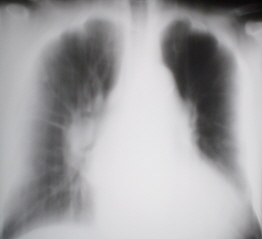

Иллюстрации 3, 4. Фрагменты рентгенограммы правого лёгкого и участка правого корня с увеличением.

Иллюстрации 5, 6. Рентгенограмма в правой боковой проекции и фрагмент с увеличением.